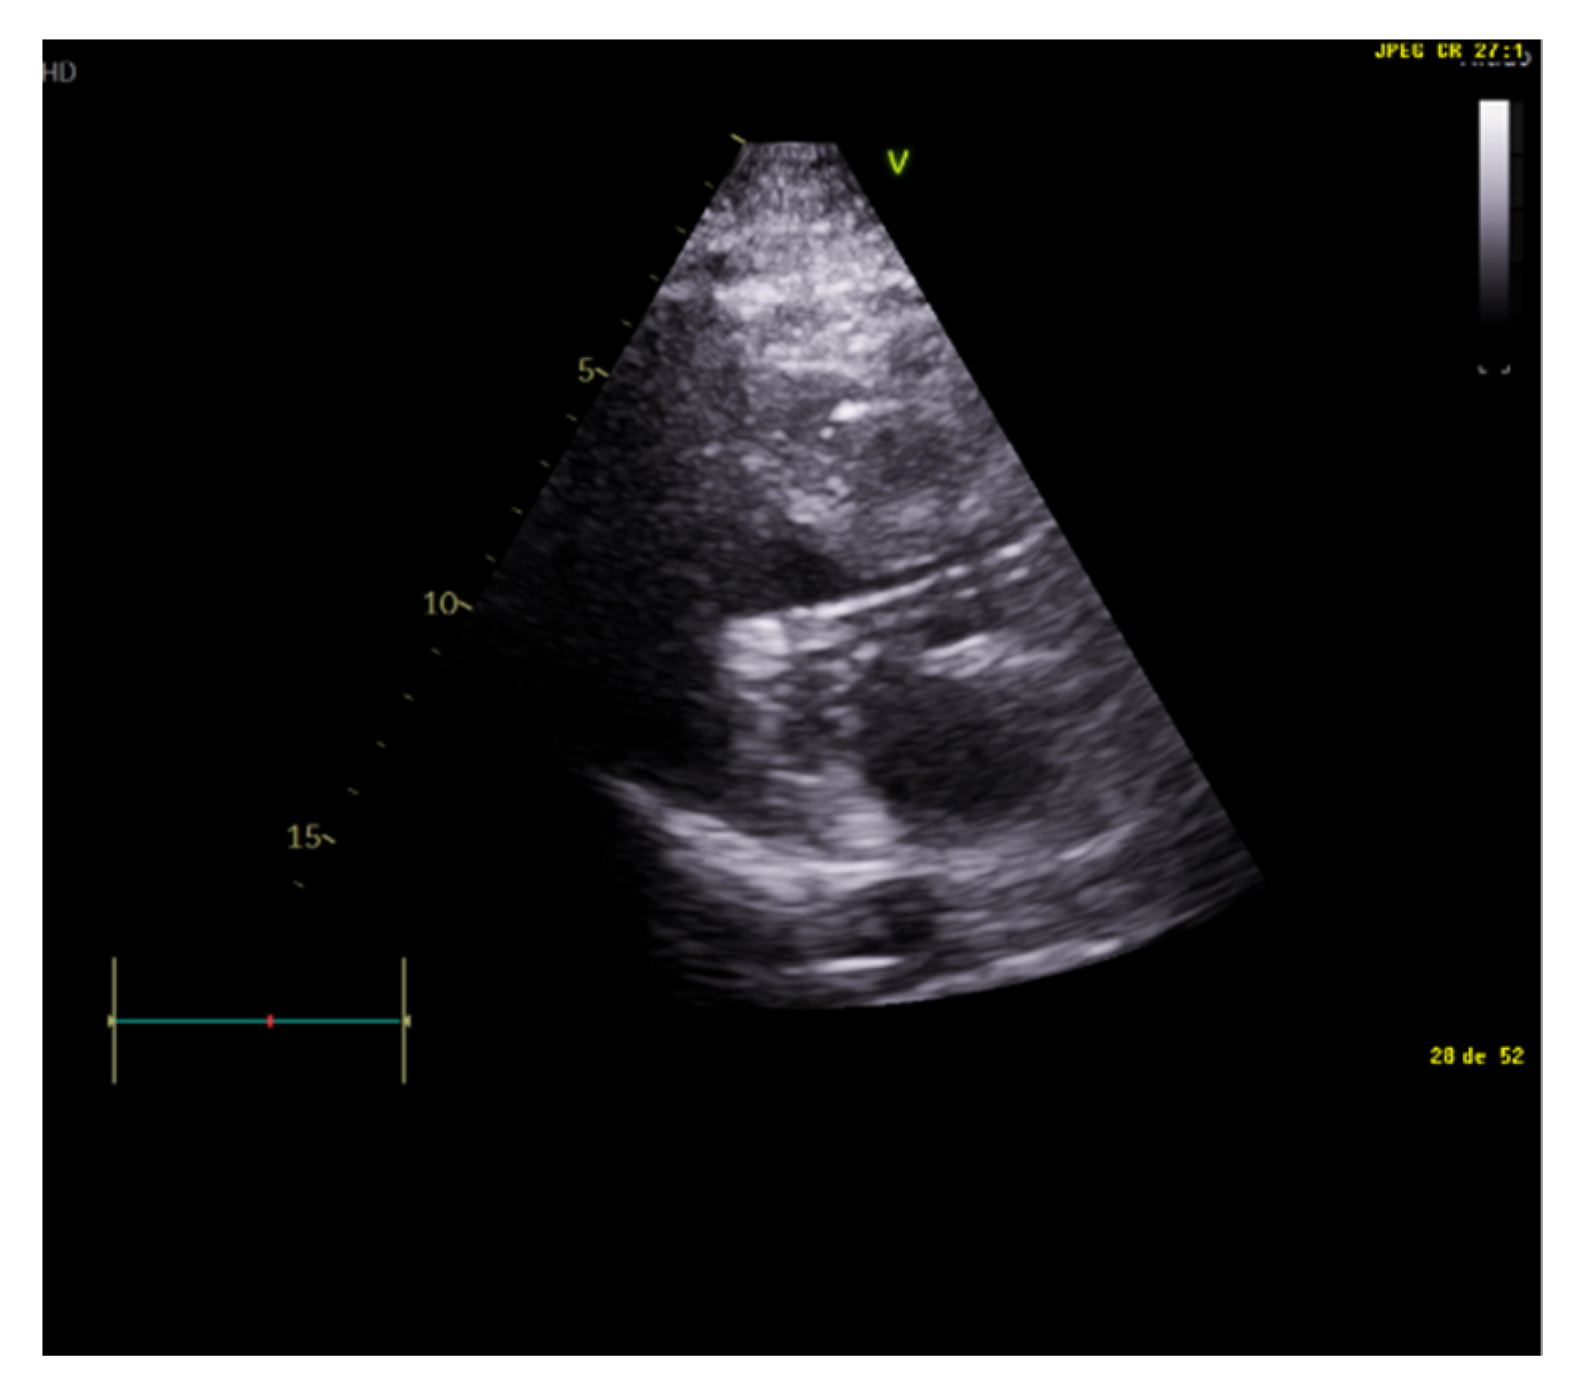

When assessing diastolic function, obtaining an E/e’ mitral ratio higher than 14.5 is associated with higher rates of weaning failure, even in atrial fibrillation [13,19,20], as are E waves higher than 0.87 m/s [13,21] (Figure 1). However, this method is less reliable in acute decompensated heart failure and left ventricles with larger volumes, where significant mitral regurgitation can lead to underestimation, as well as in resynchronization therapy and wide QRS and the subsequent change in septal e’ due to its abnormal motion [22,23].

Figure 1.

E wave height, deceleration time, and A wave. Normal filling pattern.